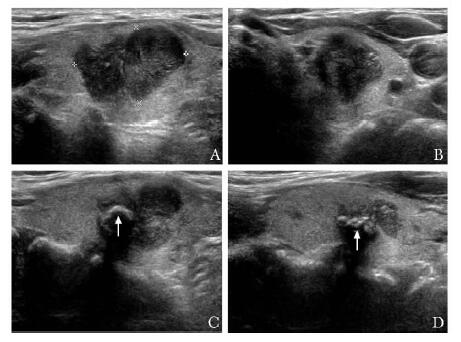

结果  CNB结果显示, 117例甲状腺病变中良性85例, 恶性28例, 可疑恶性2例, 取材不满意2例, 取材成功率98.3%;弥漫性病变37例, 甲状腺结节80例。29例手术患者术后病理显示恶性24例(22例乳头状癌, 2例淋巴瘤), 其中5例CNB为良性(假阴性); 良性5例。80例甲状腺结节中小于1 cm者2例, 1~2 cm者21例, 大于2 cm者57例。

Results  All patients completed CNB successfully and the satisfaction rate for tissue samples was 98.3%. The CNB pathologic results of 117 patients were as follows:85 cases were benign, 28 cases were malignant, 2 case were suspected malignant, and 2 cases were inadequate for diagnosis; 37 cases had diffuse lesions and 80 cases had nodules. In 29 patients (including 24 cases of malignancy and 5 cases of benign disease) who had undergone surgery, the CNB pathologic results in 5 cases were false negative compared with the pathologic results of surgery. The diameters of thyroid nodules were less than 1 cm in 2 cases, 1-2 cm in 21 cases, and more than 2 cm in 57 cases.